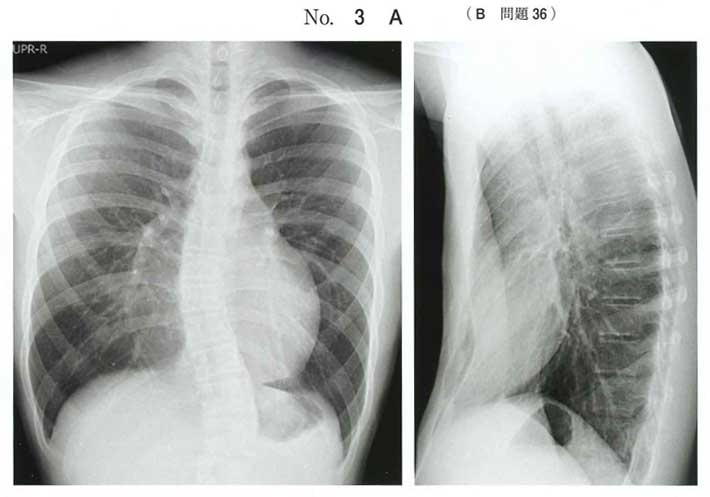

今回の提示画像(X線+CT)と設問文脈(胸郭変形の相談)からは、漏斗胸=胸骨の陥凹(b)が適切

b:漏斗胸